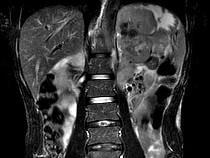

问题 男,54岁、1年前行胃癌切除术,现消瘦乏力、左锁骨上淋巴结肿大,影像检查如图,最可能的诊断是()

选项 A.淋巴瘤 B.腹膜后淋巴结转移 C.肾上腺腺瘤 D.肾上腺增生 E.腹膜后纤维肉瘤

答案 B